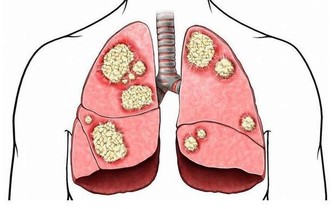

7、身邊有個大菸鬼

統計表明,美國每年有3000名非吸菸人員死於肺癌,30萬兒童患呼吸道感染,二手菸對健康的影響毋須多言。

建議:應儘量遠離二手菸環境,另外,飲酒也應適量。酒精會抑制製造抗體的B細胞,增加細菌感染的機會。